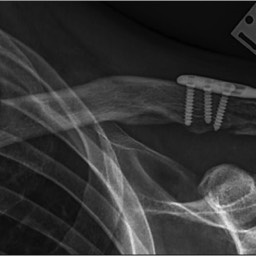

Generally all displaced fractures of the distal clavicle require surgery to increase the incidence of union. In my practice, the operation is performed by realigning the bones back to their original position using a plate and screws on top of the bone. The advantage of fixing them with a plate and screws generally means that you can start to move the arm a lot quicker and to also decrease the incidence of non-union.

How is the Operation Done?

The operation is performed with the patient under a general anaesthetic, in other words, completely asleep, and a small 3-4 cm incision is made under the collarbone, at the end of the shoulder. The fractured bone ends are exposed and put back into position using a plate and screws as shown below.

Click an image to enlarge

This fixation also needs reinforcement using special sutures around the plate and around the bone next to the clavicle called the coracoid process. The sutures are used to decrease the deforming forces from your shoulder muscles. In the majority of cases, in my hands, the operation is extremely successful resulting in the bone healing and the return of near normal function. In a small number of cases, the plate needs to be removed if it irritates the patient under the skin.